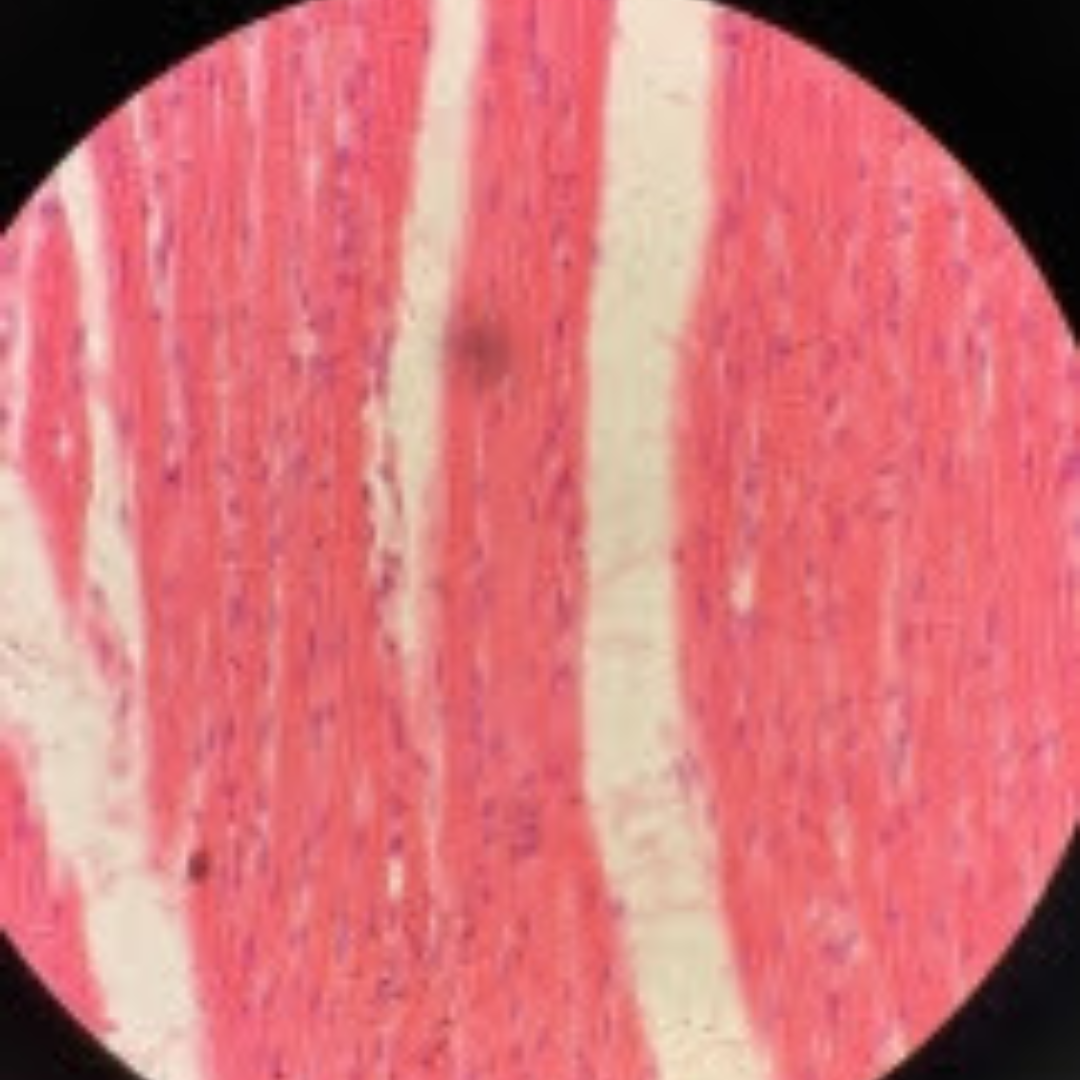

Dense Regular Elastic Connective Tissue (Elastic Tissue)